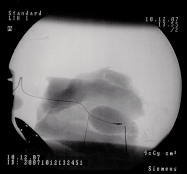

Minimal trycksensor Radis hjärtesak

Radi Medical Att avgöra när en kranskärlsoperation gör mer nytta än skada, att veta exakt var förträngningen sitter och att applicera den kärlvidgande ballongen. Det är utmaningar som förenklas av svensk medicinteknik. LÄS MER